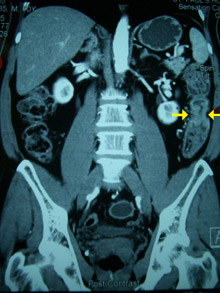

2. CT Scan

Merupakan pemeriksaan lanjutan yang non-invasif. Dengan teknologi pemindaian berbasis komputer, dokter dapat memperoleh gambaran dua dimensi (2D) maupun tiga dimensi (3D) dari kondisi usus. Jika hasil CT scan menunjukkan kelainan, pasien akan disarankan menjalani kolonoskopi untuk pemeriksaan lebih lanjut.